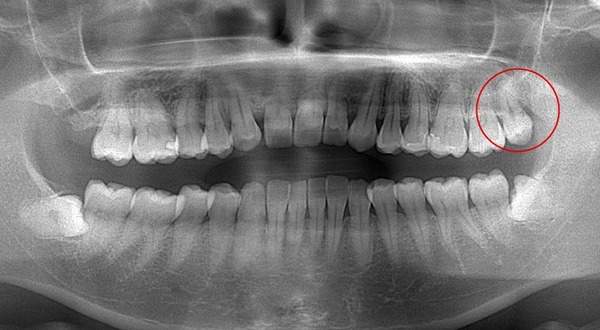

抜くのが簡単な親知らずとは

麻布十番歯科で親知らずが真っ直ぐ生えている症例のレントゲン写真のイメージ

逆に抜くのが簡単なケースは、真っ直ぐはえている上顎の親知らずです。上顎は下顎よりも骨が柔らかく、かつ根が真っ直ぐになっていることがおおいです。そのため抜くのが簡単な傾向にあります。